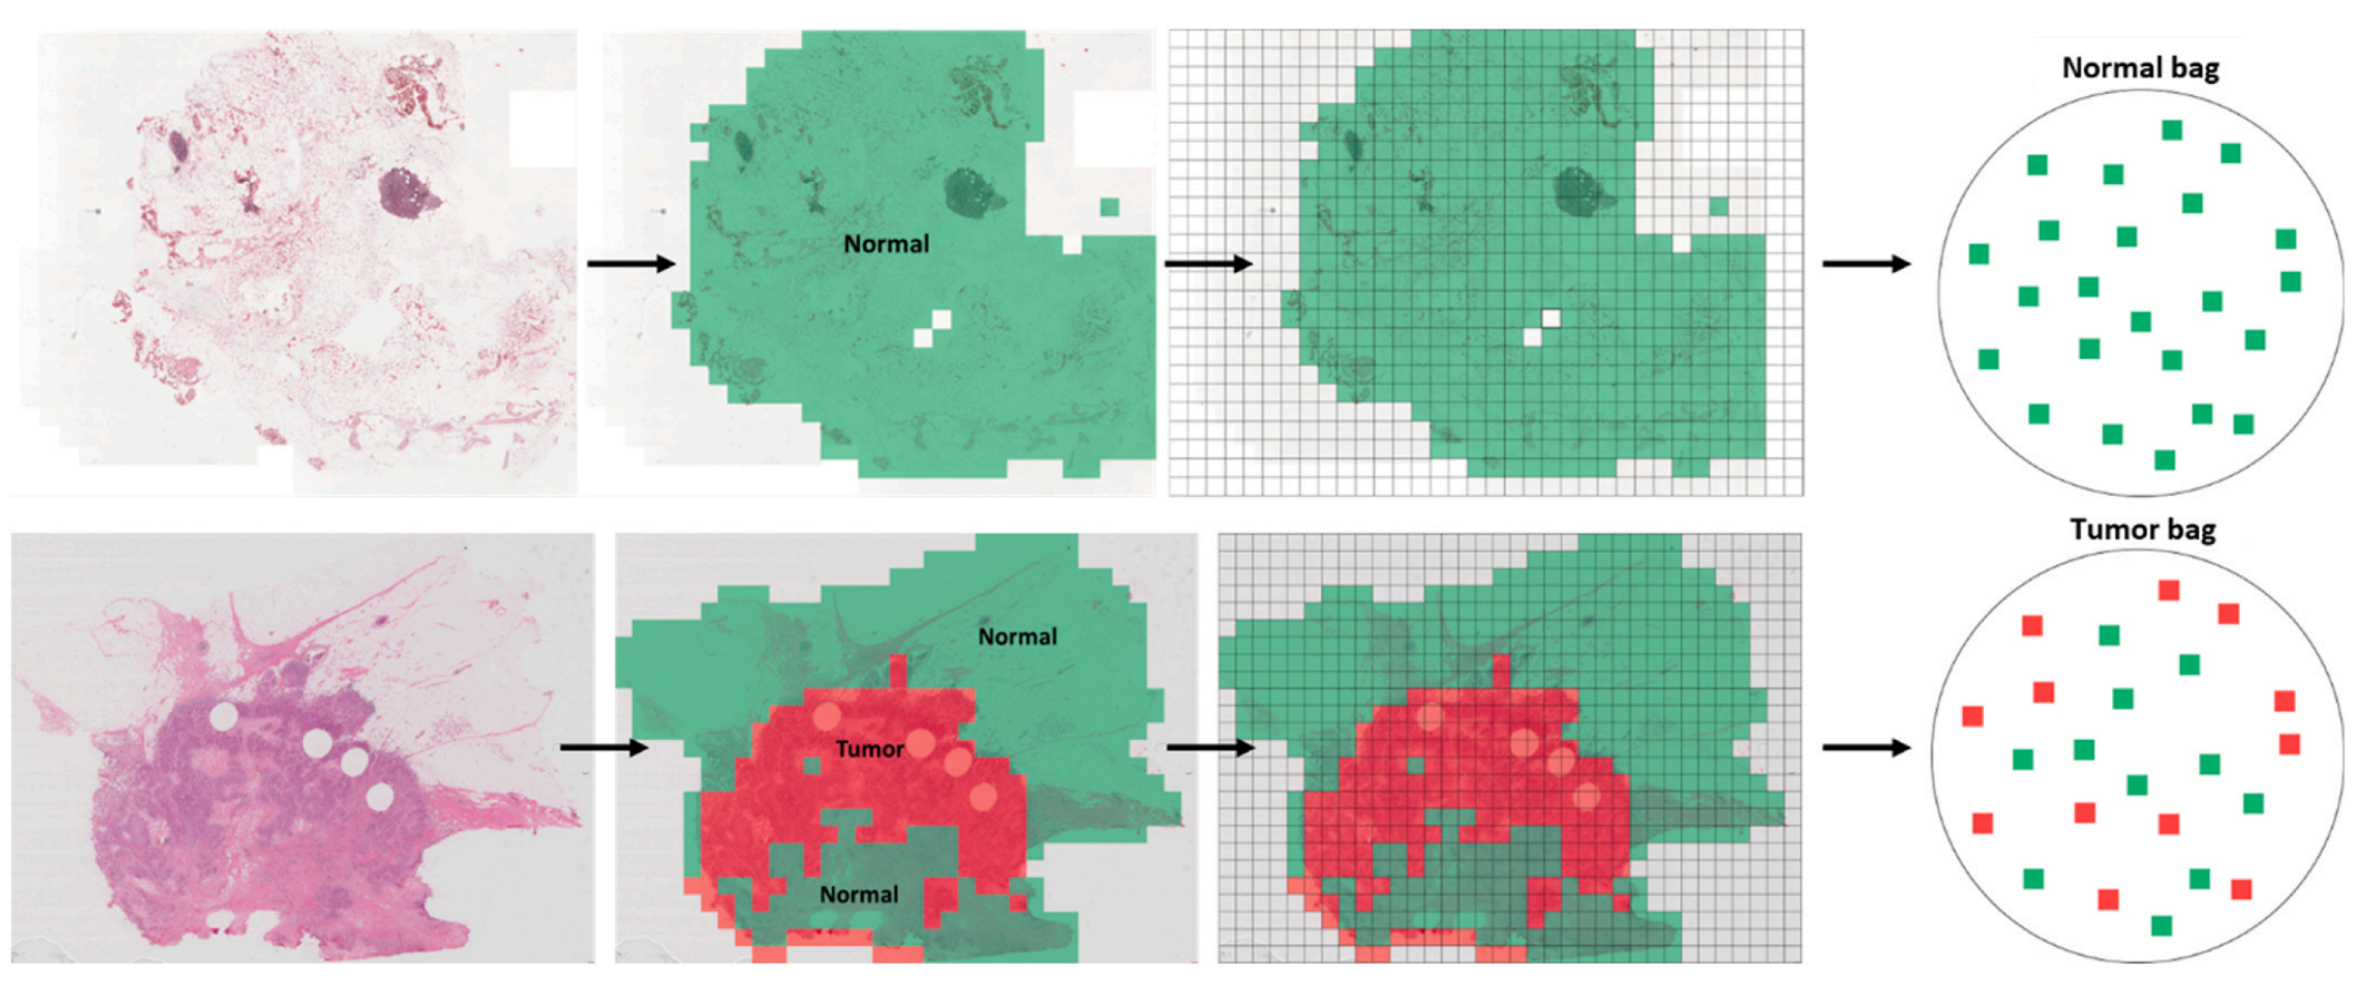

Fig. 1 展示了多实例学习(MIL)和弱标注的概念。

在MIL中,数据被组织成“包”(bag),每个包包含多个“实例”(instance)。弱标注意味着每个包只有一个标签,而不是每个实例都有一个标签。

图的上半部分展示了正常组织切片图像(WSIs),这些图像只包含正常实例(用绿色图像块表示)。在这种情况下,我们假设从该WSI派生的每个实例隐含地都是正常的。因此,生成的包由正常实例组成,并被弱标注为“正常”用于MIL。

图的下半部分展示了肿瘤组织切片图像,这些图像包含肿瘤实例(用红色图像块表示)和正常实例。在这种情况下,我们假设一些实例隐含地是肿瘤,而另一些实例隐含地是正常的。因此,生成的包包含肿瘤和正常实例,并被弱标注为“肿瘤”用于MIL。

图中的绿色和红色注释仅用于说明目的,MIL框架无法访问这些注释。这意味着MIL算法必须在没有任何具体实例级别标注的情况下,通过整体的包标签来学习识别和区分肿瘤和正常组织。

分析这个图,我们可以得出以下几点:

-

弱标注的优势:通过弱标注,可以减少对每个实例进行详细标注的工作量,这在组织病理学图像分析中尤其有用,因为病理学家通常缺乏时间进行大量的像素级标注。

-

MIL的工作原理:MIL算法通过分析整个包的内容来推断包的标签。在肿瘤检测的上下文中,算法需要学会区分包含肿瘤的实例和不包含肿瘤的实例。

-

实例的隐含标签:在正常WSI中,所有实例都被认为是正常的;而在肿瘤WSI中,实例可能是正常的也可能是肿瘤的,这增加了MIL算法学习任务的复杂性。

-

可视化辅助:虽然注释用于帮助理解,但在实际的MIL框架中,算法需要独立地从数据中学习模式,而没有直接访问这些可视化辅助。

-

应用前景:这种弱监督学习方法为开发能够处理大规模组织病理学图像的AI系统提供了一种有效的途径,有助于在资源有限的情况下提高病理诊断的效率和准确性。